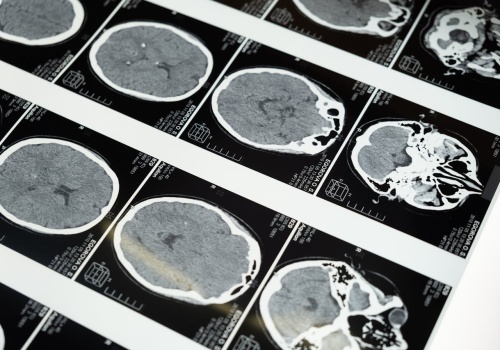

Nowe badanie wskazuje, że blokowanie białka CD47 może ograniczyć wzrost i inwazyjność glejaka wielopostaciowego – jednego z najgroźniejszych nowotworów mózgu. Artykuł Blokowanie białka CD47 może spowolnić rozwój guza – nowy cel leczenia glejaka wielopostaciowego pochodzi z serwisu Alert Medyczny.